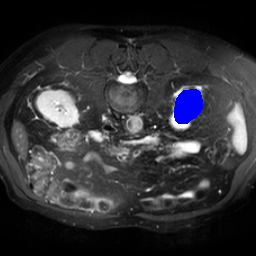

Support

Label

Proposed

In order to assess the performance of the proposed method, we compare the performance of the proposed model with excellent models in recent years. Table 1 and Table 2 shows the comparison results of different models in setting1, while Table 3 and Table 4 shows the comparison results of different models in setting2 on the data set in recent years. PANet[25] is the most widely influential few-shot model in the field of few-shot image segmentation on natural images. SENet [18] is the first few-shot segmentation model proposed for medical images. SSL-ALPNet[19] introduced the milestone of using superpixel self-supervision to train few-shot medical image models. RPNet[29] is a supervised method with a recursive mask optimization module to iteratively optimize the segmentation mask, [27] adapt it into the same self-supervision learning framework and applies setting1 to it and denoted as SSL-RPNet; CRAPNet[27] is the latest SOTA model for 2023. Compared with CRAPNet, our method outperforms most of the state-of-the-art models and only slightly outperforms CRAPNet. Figures 3 and 4 show examples of the model’s segmentation predictions on different datasets, respectively; The first row is the support map, the second row is the label map, and the third row is the segmentation prediction of the model.